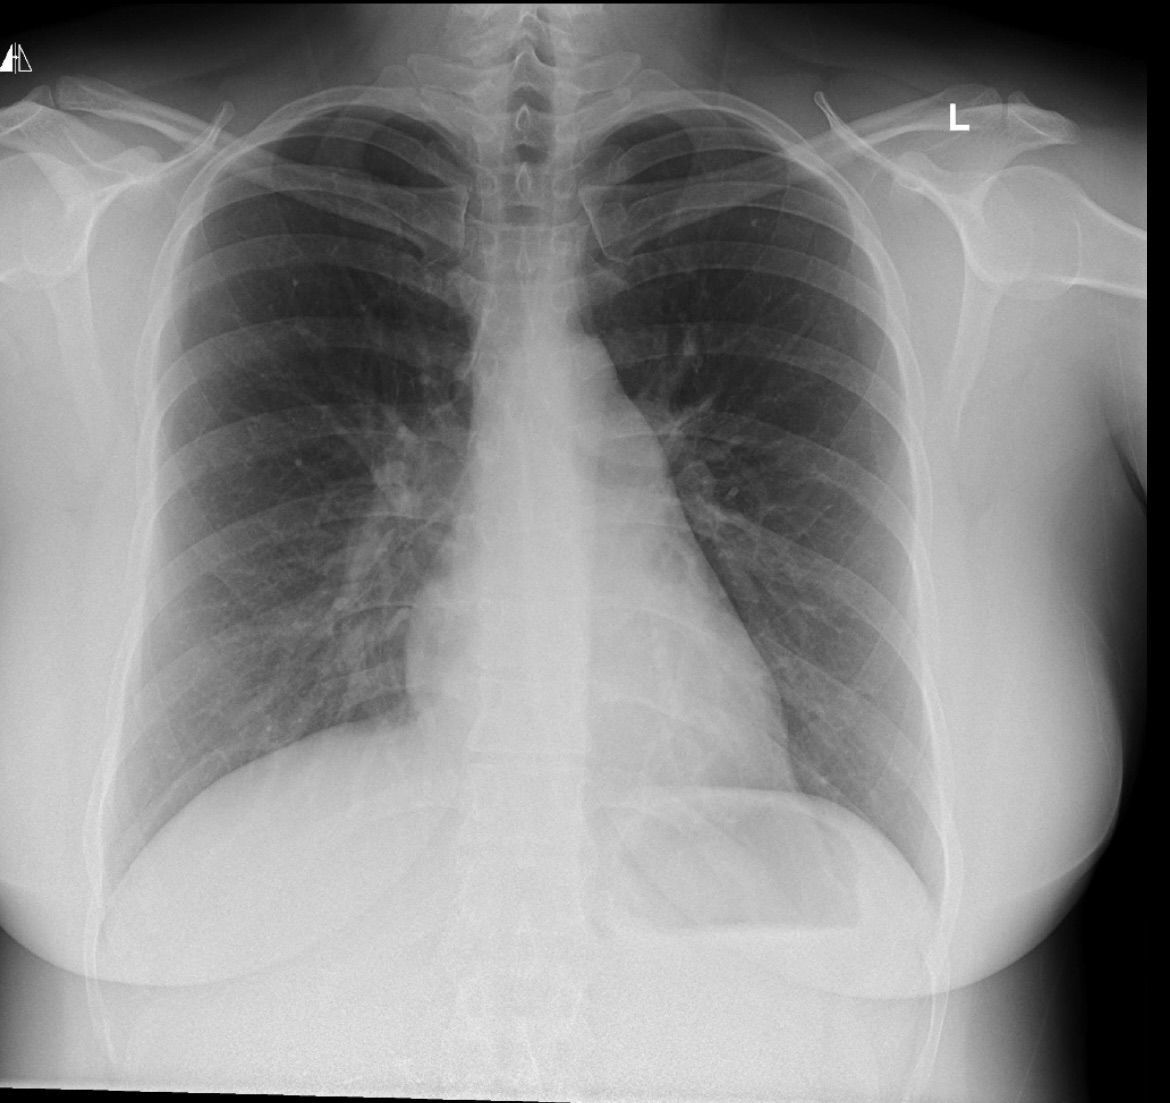

34y/o female chest xray

1 week history of cough, recent deep cough with mucus production. ?diagnosis